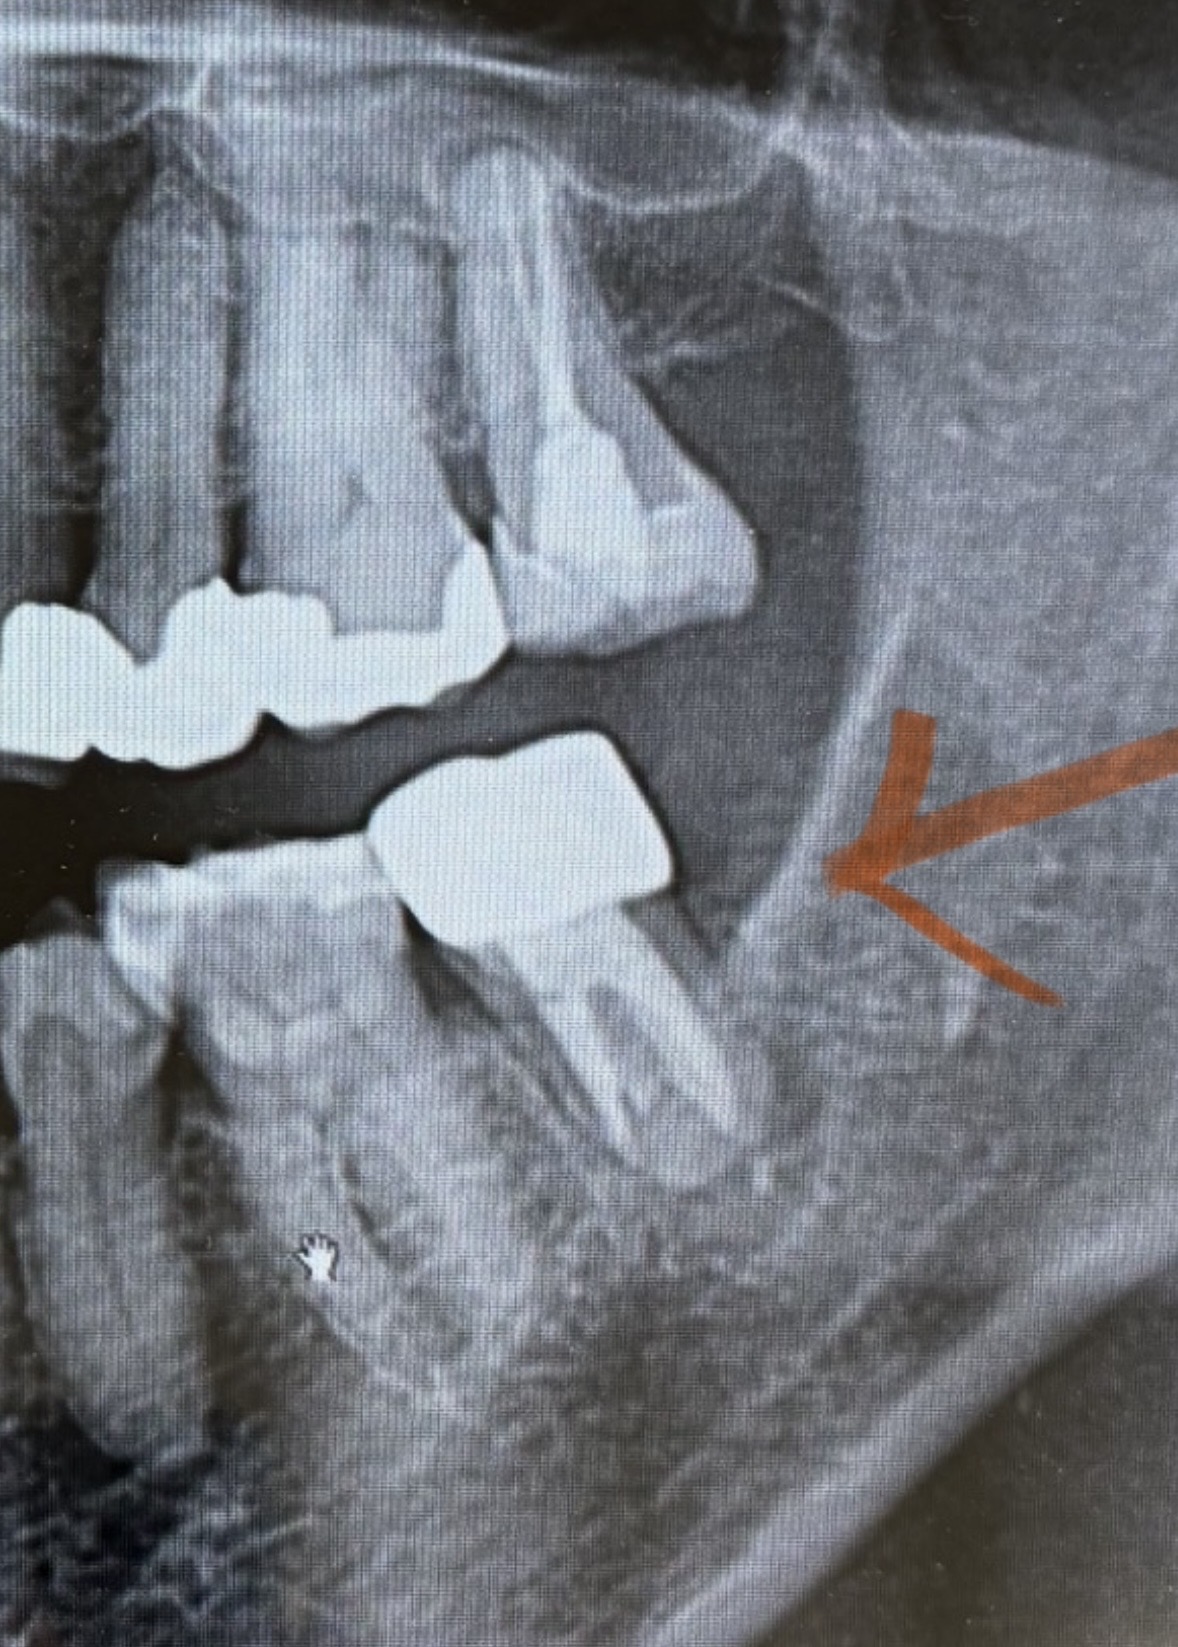

歯の根の下に黒っぽい場所(黄緑でマーキング親知らず側)があってそこから歯茎の方に膿が出ている。

CT画像からはハッキリ破折を認められない。

少し線が見える場所が6番の歯側にあるが、黄緑でマーキングした場所は根幹治療で薬が入っているところと根の治療の境目で破折ではない可能性もある とのこと。

奥歯7番は根幹治療をしてもなかなか難しい場所で、根の形がCTで見ると、Cという文字のようなかたちでつながっていると、余計難しいとのことでした。